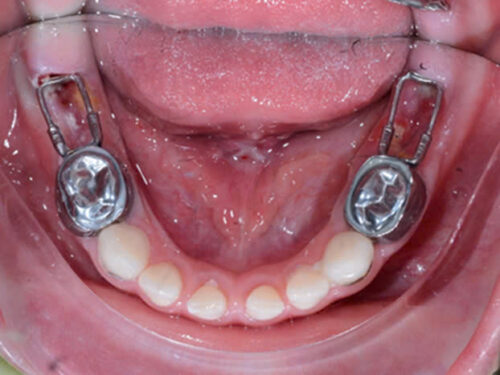

Cung lưỡi giữ khoảng khi mất răng 2 bên